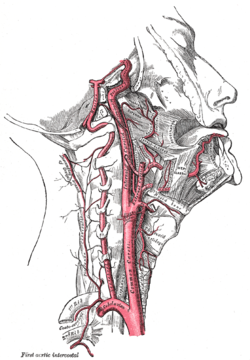

شراين متفرعة من العنق. تتفرع الشرايين السباتية الغائرة من الشرايين السباتية الأصلية - موضحة على الشكل باسم Common caroti on the figure.

الشريان السباتي الغائر، يقع على الجانب الداخلي من العنق على الجانب المقابل للشريان السباتي الظاهر.[1] في التشريح البشري، تتفرع الشرايين السباتية الغائرة من الشرايين السباتية الأصلية حيث تتشعب هذه الشرايين السباتية الغائرة والظاهرية عند مستوى الفقرة العنقية 3 أو 4؛ يوصل الشريان السباتي الغائر الدم للمخ بما في ذلك العينين،[2] بينما يوصل الشريان السباتي الظاهري الدم لمناطق أخرى في الرأس، مثل الوجه، فروة الرأس، الجمجمة، والسحايا.

الفروع

يتم تزويد المخ بالدم عن طريق 4 شرايين هي الشريانان السباتيان الغائران والشريانان الفِقريان[3]. لا يتفرع الشريان السباتي الغائر حتى يدخل الجمجمة من خلال النفق السباتي أسفل الجمجمة. بعد دخول الجمجمة يسير الشريان السباتي على شكل حرف S إلى جانب السرج التركي (باللاتينية: Sella turcica) مروراً بالجيب الكهفي (باللاتينية: Sinus cavernosus) لينقسم إلى فروعه الرئيسية:

ثم يتغير أسم الشريان السباتي الغائر ليشكل الشِّرْيانُ المُخِّيُّ الأَوسَط، هذا الشريان الذي يعتبر امتداداً للشريان السباتي الغائر، والذي يزود الجزئين الجانبيين من الدماغ.